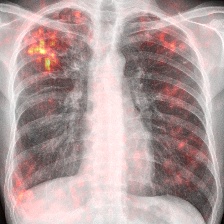

Figure 1: Overview of marginalization: (a) original with annotated mass (red box) before and after marginalization by our method; (b) local comparisons with popular methods (clockwise): original, blurring [9], inpainting (ours), and averaging [29]; (c) ROC curves of the mammography classifier (green curve) vs. healthy pixel inpainting only in healthy/pathological (blue/red curves) structures.

Thus, we computed ROC curves using the classifier on all test samples (i) without any inpainting as reference, and for comparison, randomly sampled inpainting (ii) only in healthy respective (iii) pathological scans over 10 runs (Fig. 1). The clear distance between the ROC curves of the mammography image classifiers without any inpainting, yielding an AUC of 0.89, and with inpainting in pathological regions, resulting in an AUC of 0.86, shows that the classifier is sensitive to changes around pathological regions of the image. Moreover, it is visible that the ROC curves of inpainting in healthy tissues with an AUC of 0.89 follow closely the unaffected classifier’s ROC curve (Fig. 1). The AUC scores for the TBC classifier without and with inpainting in healthy tissue are 0.89 and 0.88 which proves the above mentioned observations. Pathological tissue inpainting was ommitted in this case due to the lack of pixel-wise annotations.